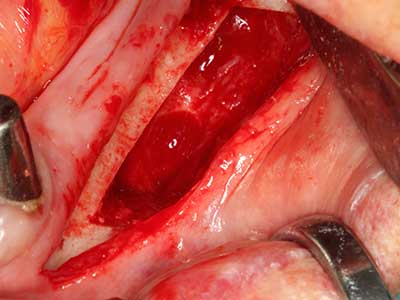

Sollen chirurgische Eingriffe mit unmittelbarer Knochenbeziehung an empfindlichen Strukturen wie Blutgefäßen oder Nerven erfolgen, so bergen rotierende Instrumente ein erhebliches Potential an iatrogener Schädigung. Gerade bei Nervdarstellungen nach iatrogener Schädigung, oder aber im Zuge einer Nervlateralisation für resektive und rekonstruktive Eingriffe oder Implantatinsertionen können piezoelektronische Geräte hilfreich sein Knochendeckel zu präparieren und nervnahe Hartgewebsanteile zu entfernen (Abb. 17-20). Ein leichter Kontakt des Nervstrangs zur Piezospitze bleibt dabei in der Regel folgenlos – allerdings kann eine unvorsichtige Vorgehensweise mit sägeartigen Bewegungen bzw. Ansätzen bei noch vorhandener knöcherner Unterlage durchaus temporäre oder aber auch permanente Nervschädigungen verursachen. Das Risiko einer solchen Schädigung wird jedoch als wesentliche geringer eingeschätzt als unter Anwendung von Säge- oder Fräsinstrumenten (Pereira, Gealh et al. 2014).